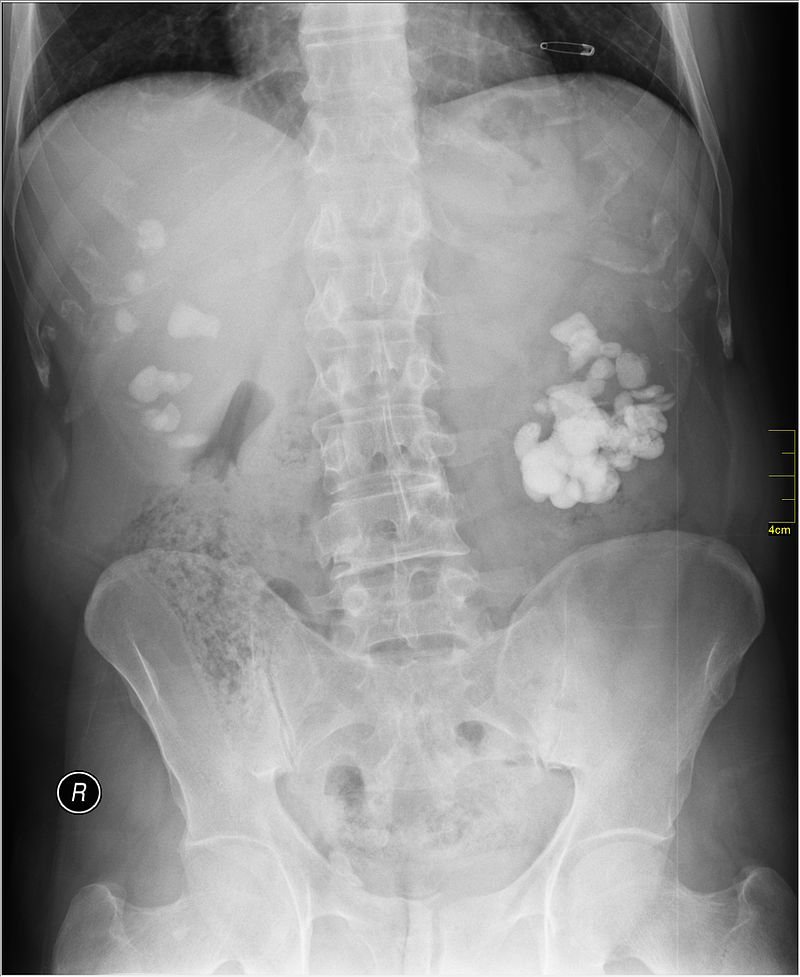

ASP – Chụp Xquang bụng không chuẩn bị

Đa phần sỏi hệ tiết niệu ở Việt Nam là sỏi cản quang nên chỉ định chụp Xquang rất có giá trị trong chẩn đoán. Biện pháp này giúp bác sĩ xác định vị trí sỏi cản quang, cho biết kích thước số lượng và hình dáng của sỏi.

UIV – Chụp hệ tiết niệu qua đường tĩnh mạch

Chụp UIV cho biết hình dáng thận, đài bể thận, niệu quản; vị trí của sỏi trong đường tiết niệu và mức độ giãn nở của đài bể thận, niệu quản. Thông qua đó có thể xác định được chức năng bài tiết chất cản quang của thận từng bên.